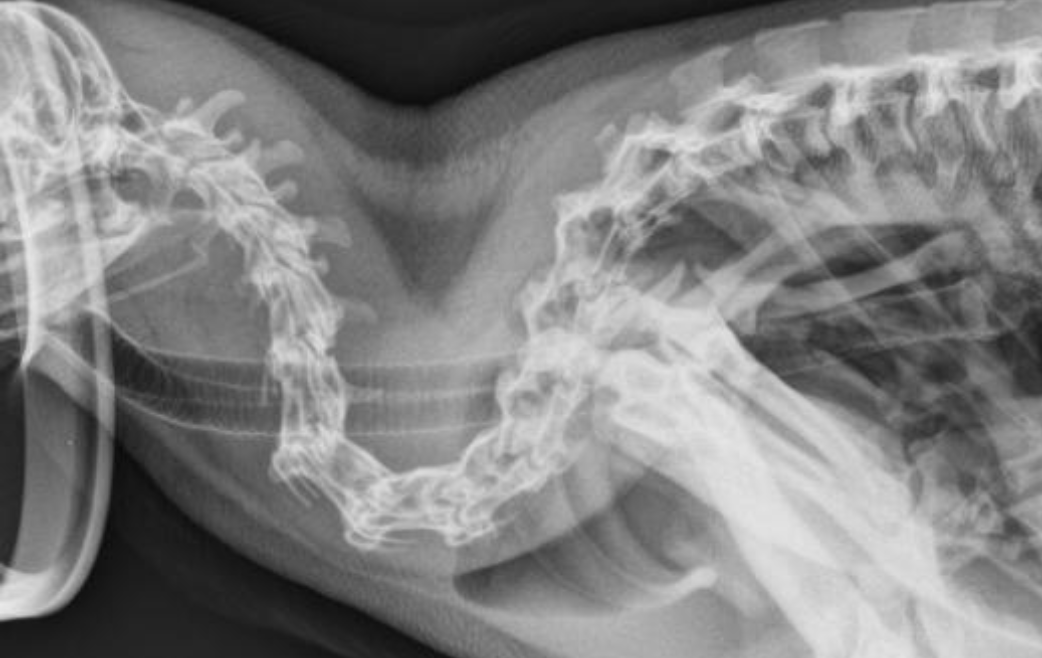

What is this “odd normal” that occurs in ducks?

A

syringeal bullae